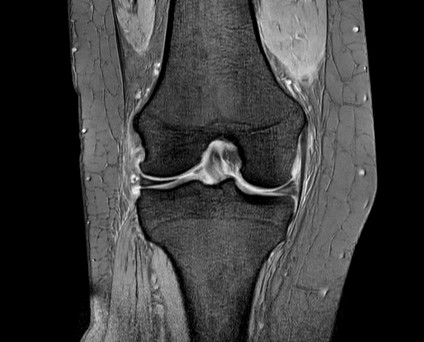

整形領域の撮影

当センターでは、体幹部のみならず四肢の撮影も行っております。膝関節、肩関節、手関節、足関節など整形領域の撮影も行っております。最新のAI技術を用いることで、より細かく描出できるようになり、靭帯損傷や骨折、筋損傷を見つけることが出来ます。

『膝関節MRI画像』